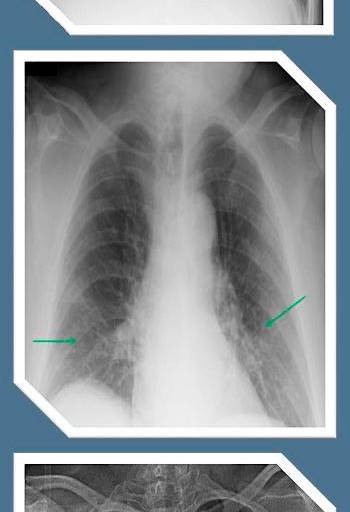

En el caso de las enfermedades respiratorias, la información disponible indica que también las personas asintomáticas, las que no tienen o tuvieron síntomas muy graves y aquellas que no fueron hospitalizadas presentan porcentajes de fibrosis en los pulmones.

“Eso definitivamente deja un órgano disfuncional y muchas personas han tenido que reaprender a respirar para aprovechar ese 50 por ciento de pulmón que les queda. Eso es una condición incapacitante”.